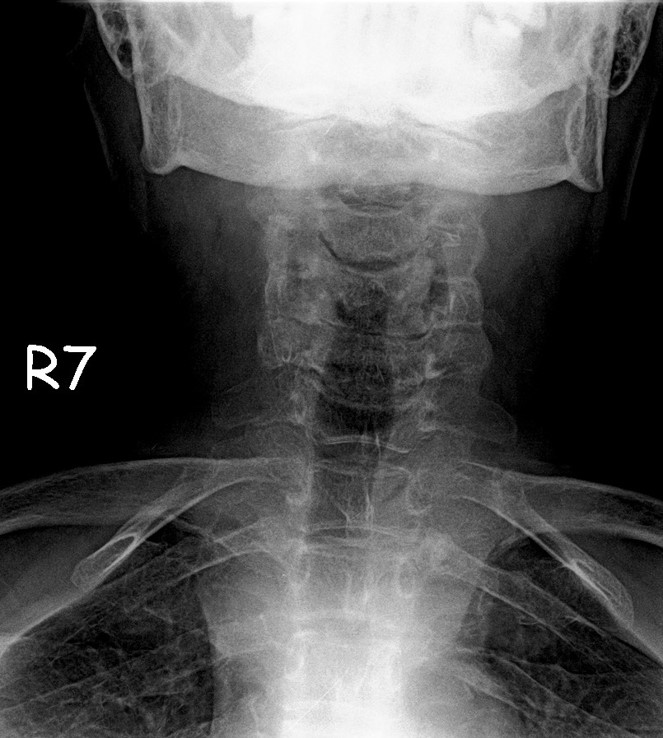

Ameliyat Sonrası